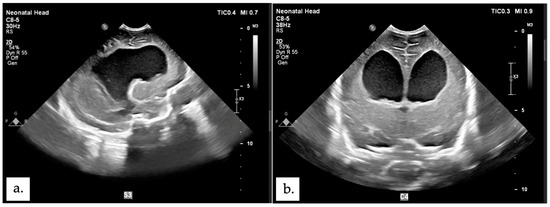

2.1. Patient 1

2.2. Patient 2

2.3. Patient 3

2.4. Patient 4